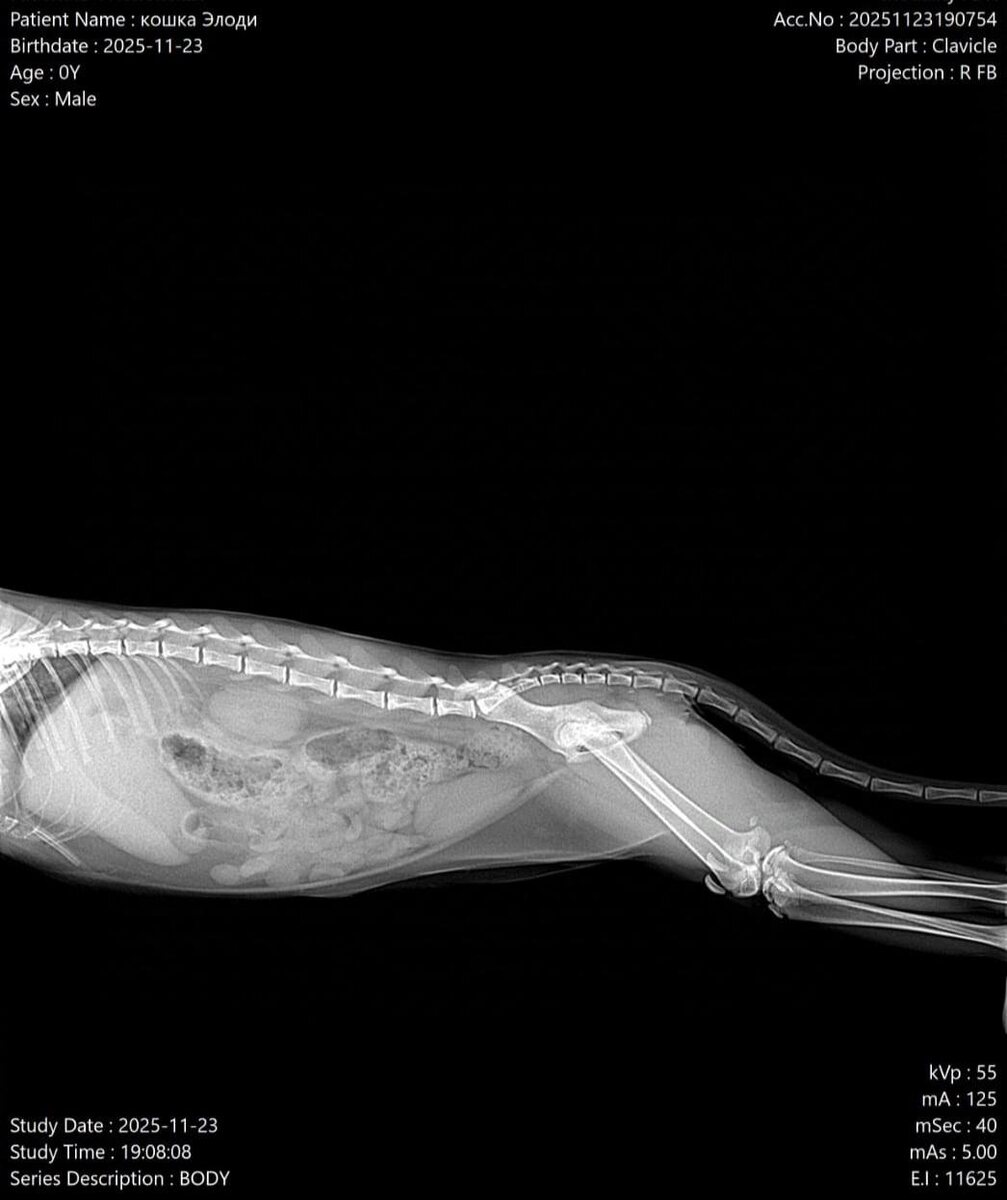

По-началу с котенком все было хорошо — малыш рос и играл, как обычный котенок своего возраста. В какой-то момент питомец стал хромать, а потом и вовсе с трудом ходить. По словам сотрудников приюта, задние лапки у Элоди (так назвали питомца) были в странном положении, и попросту не сгибались.

В ветклинике сообщили плохую новость — у малышки врожденный вывих коленных суставов.

- Ни приют, ни две ветклиники, в которых занимались малышкой, пока не сталкивались с подобными случаями у таких маленьких котят, - подчеркнули волонтеры.